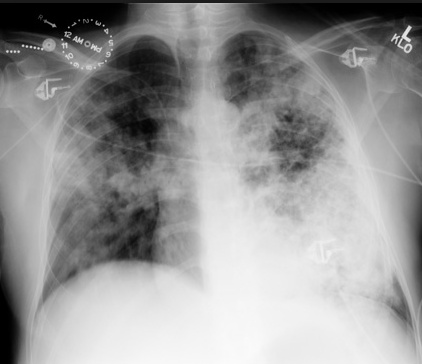

lung with cannon balls: Chest X-ray has patchy alveolar infiltrates/haziness

cannon balls in lung: Lesions or cavities in lungs

plane with letters. Farmer running/migrating, sweating, inhaler in hand: ABPA (allergic bronchopulmonary aspergillosis) is a type I HSR that causes wheezing, fever and migratory pulmonary infiltrates. Also association with CF patients

glass tables with cracks: "Ground glass" appearance on chest X-ray